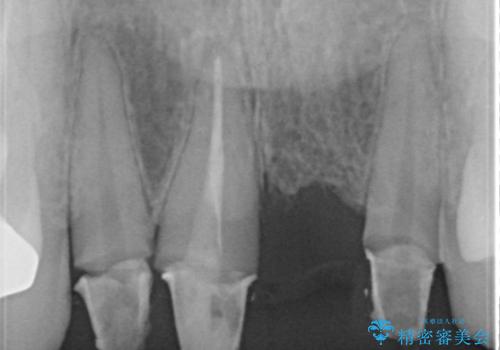

3年間仮歯 前歯セラミックブリッジ

- 3年間仮歯のまま過ごしていたそうです。 色の変色と臭いが気になり来院されました。

- 61万6千円 (根管10万x1本 コア1万x1本 仮歯1万x4本 セラミック(スタンダード)10万x4本)費用は治療当時の料金となります